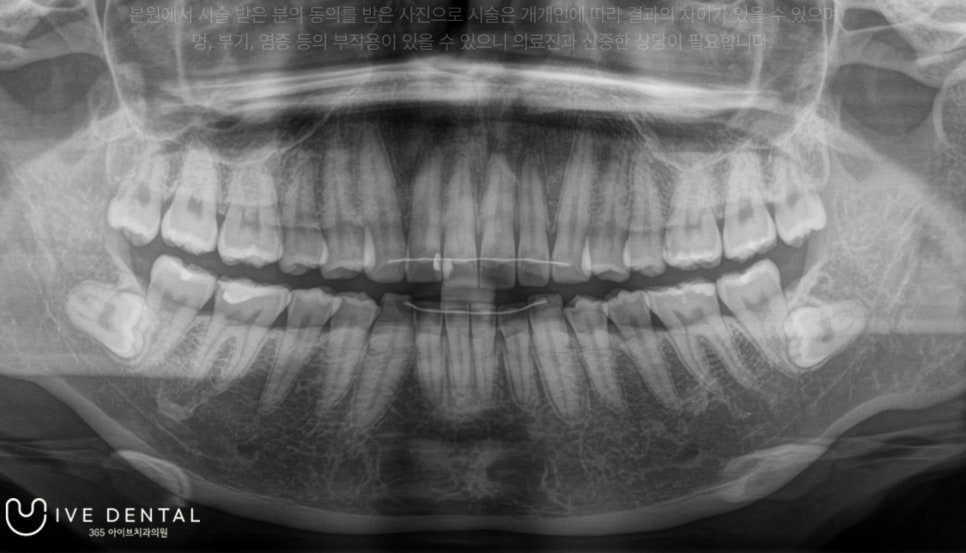

돌출 사랑니와 매복사랑니가 있는 30대 환자분

군산에 사시는 30대 여성 환자분이신데요!

​양쪽 상악에 돌출 사랑니와 하악에 매복 사랑니가 보입니다.

환자분께서는 전부터 매복사랑니 부위에 간헐적으로 통증이 발생하여 발치를 하고 싶으셨지만, 매복사랑니라서 군산에 다니시던 기존 치과에서 발치가 불가능하였고 큰 병원에 가보기를 권유받으셔서 저희 병원에 내원하셨습니다.

저희 아이브치과에서는 양쪽 사랑니 4개 모두 하루에 발치 진행이 가능하지만, 환자분께서는 왼쪽 사랑니부터 발치를 원하셨습니다.